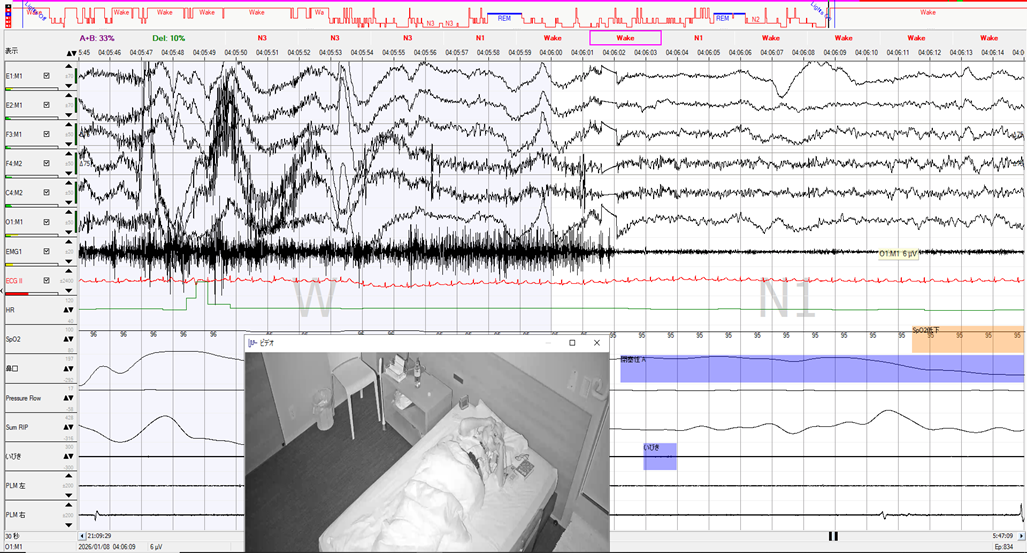

YUMINO'S コラム ゆみのPSGケースカンファ 学会・研究会 主要講演歴 著書出版歴 臨床研究 その他の活動 ゆみのPSGケースカンファ 2026年05月08日 記録前半は閉塞性呼吸イベントが主体で朝方CSR様の周期性呼吸を認めた症例 2026年05月01日 記録前半は閉塞性呼吸イベントが主体で朝方CSR様の周期性呼吸を認めた症例 2026年04月24日 超重症OSA症例の無呼吸と低呼吸 2026年04月14日 やせ型・若年者 でも重症のOSA症例 2026年04月10日 側臥位の就寝時間が長かったにも関わらず、重症の結果だったOSA症例 2026年04月03日 ノンレム睡眠側臥位の安定呼吸時の持続的なSpO2低下 2026年03月27日 CPAPタイトレーションで中枢性無呼吸が残存した症例 2026年03月13日 簡易検査結果と乖離して、大きく軽症化した症例 2026年03月06日 低振幅脳波で入眠判定が困難だったOSA症例 2026年02月27日 側臥位でも呼吸イベントが抑制されない重症OSAと徐波群発 1 2 3 4 5 年別 2026年 2025年 2024年 カテゴリー別